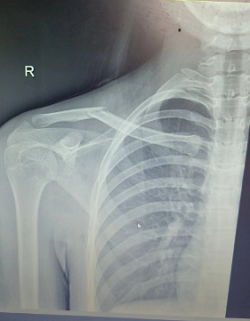

微创治疗锁骨骨折,让您拥有漂亮的“美人骨”!

15岁的小周是一个成绩非常优秀的女孩子,一次意外后出现锁骨骨折。锁骨骨折了那怎么办?这可愁坏了父母!要是按照传统治疗那就这样:手术切口像个“蜈蚣”样,影响了美观。小周父母实在是发愁,到处打听,了解到了我院骨科可以进行微创手术治疗,切口小,恢复快,于是将孩子带到我院就医。我院骨科丁晔医师查看后,对患者采取微创闭合复位经皮弹性髓内钉内固定术。手术属于微创手术,仅需0.5cm的小切口从锁骨远端或锁骨近端为进针点...